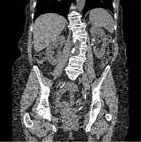

従来法

逐次近似法